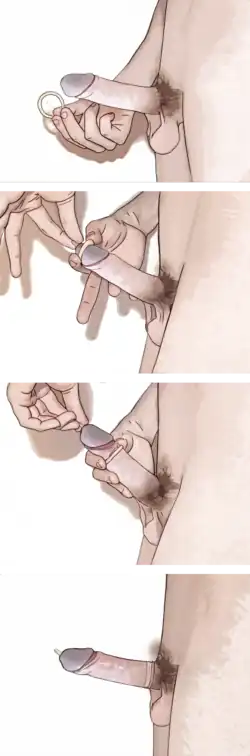

Pohlavní styk může, ale nemusí být zakončen orgasmem (vyvrcholením) a ejakulací jednoho nebo více partnerů. Prožívání pohlavního styku je individuální a kromě genetických dispozic hraje roli také zdravotní stav, věk, zkušenosti, fyzická a psychická kondice, hladina pohlavních hormonů a další faktory.[5] Období, kdy dochází prvnímu pohlavnímu styku člověka, se může různit podle kultury. V moderním českém prostředí jde průměrně o dobu mezi sedmnáctým a osmnáctým rokem života, o něco dříve než v minulosti.[6] Podobně jako u mnoha druhů zvířat má u člověka pohlavní styk význam nejen při množení druhu, ale i jako společenský akt. V moderní západní společnosti většina pohlavních aktů se snahou o rozmnožení nesouvisí a je vnímána jako rekreační.[7] Předpokladem tohoto přístupu je využívání antikoncepce, tedy metod k zabránění početí (přerušovaná soulož, prezervativ, pesar, hormonální antikoncepce a podobně).[8]

Pro oba účastníky sexuálního styku je vhodné uvážit, že jejich aktivita může velmi pravděpodobně způsobit těhotenství, nepoužijí-li adekvátní antikoncepční prostředky. Ale i pak je nutno možnost těhotenství připustit, protože žádná antikoncepce není 100% efektivní. Přerušovaná soulož (coitus interruptus) neboli „vytažení“ penisu z pochvy před ejakulací za efektivní metodu antikoncepce považována být nemůže a nelze ji doporučit. Jediné zcela spolehlivě fungující metody vyhnutí se těhotenství jsou sexuální abstinence a sterilizace. Externí styk, tedy sexuální aktivita bez vložení penisu do pochvy, může být prováděna bez rizika těhotenství za předpokladu, že spermie nepřijdou do kontaktu s vulvou (ženským zevním pohlavním ústrojím).

Antikoncepce

Bezpečný sex, například používání mužského nebo ženského kondomu, může rovněž sloužit nejen jako prevence sexuálně přenosných infekcí, ale i k omezení rizika těhotenství. Spermicidy jsou látky, které se používají s kondomy a dále omezují pravděpodobnost těhotenství.

K nejspolehlivějším metodám antikoncepce patří sterilizace vasektomií u mužů a podvázáním vejcovodů u žen, nitroděložní tělíska (IUD) a implantovaná antikoncepce. Hormonální antikoncepce je aplikována například jako orálně podávané tablety nebo náplasti a jinými formami. K méně spolehlivým metodám patří bariérová antikoncepce – kondomy, poševní pesary a antikoncepční houbičky a různé metody sledování plodnosti. Sterilizace je sice vysoce spolehlivá metoda, obvykle je ale nevratná. Nouzová antikoncepce může zabránit početí ještě několik dnů po nechráněném pohlavním styku.

Antikoncepce

Antikoncepce zahrnuje metody a prostředky, které se používají k zabránění těhotenství. Zcela bezpečným, z hlediska nežádoucího těhotenství činí pohlavní styk kastrace. Přerušovaná soulož, soulož do konečníku, vzájemná masturbace a orální sex patří mezi metody, které snižují riziko těhotenství.